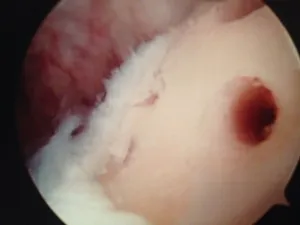

A series of intraop ankle arthroscopy pics of synovial chondromatosis with OCD talus and tibia and microfracture.

Pic of one of the nodules inside the ankle joint.

Pic of an OCD in the talar dome due to pressure from the nodule.